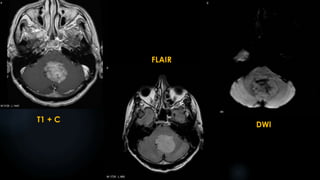

Medulloblastoma (contd.)

 MRI:

 Hypointense on T1

 Variable hypo‐ to hyperintense on T2

 Variable enhancement

 restricted diffusion on diffusion-weighted imaging

T1

T1 + C

FLAIR

Gradient Echo DWI